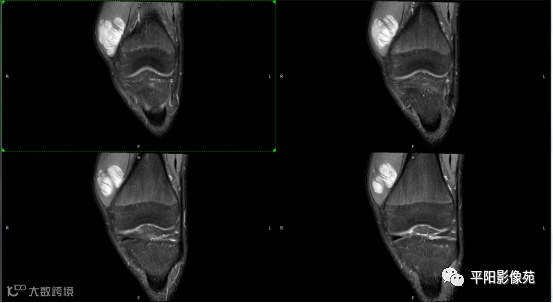

影像表现:

左膝关节股内侧肌内见多房样短T1长T2信号,内可见分隔,增强扫描明显强化,分隔未见明显强化,病灶局部与股骨远端分界不清。

MRI表现:好发于下肢, 较大病灶多为与肢体长轴一致的梭形, 边缘不清, 较小病灶呈类圆形, 边缘较清;②T1WI呈等或稍高信号, 病灶内部或边缘可见线条状或花边状高信号灶, 类似于皮下脂肪信号, T2WI上为明显高信号, 为本病特征性MRI表现;③病灶内静脉石及血管流空影为又一特征MRI表现;④GD-DTPA增强, 病灶明显强化, 其内低信号间隔无强化;⑤可见骨外形改变, 骨质增生及骨质吸收等表现。